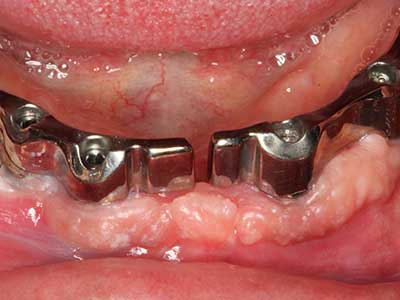

Aplicación: Preparación cerca del nervio

Como ya se ha mencionado, en el ámbito de la odontología conservadora también existen áreas en las que está indicada la cirugía piezoeléctrica. El uso de insertos de trabajo especiales facilita la representación del ápice radicular y, sobre todo en el área de los premolares inferiores y superiores, protege mejor los nervios y las mucosas del seno maxilar. En el caso de un cierre apical no estanco, los insertos de diamante acodados preparan de forma exacta y selectiva la cavidad de resección para el material de relleno retrógrado de la raíz. Gracias a la técnica de ultrasonidos, los insertos pueden presentar un diseño muy estilizado, lo que mejora la visión global y el tamaño de la cavidad de acceso. De este modo, en esta indicación, el uso de la cirugía por ultrasonidos se encuentra entre los métodos estándar para una apicectomía (Del Fabbro, Tsesis et al. 2010, Scarano, Artese et al. 2012).

Aplicación: Apicectomía

Si es preciso realizar intervenciones quirúrgicas en las que el hueso está en contacto directo con estructuras sensibles, como son los vasos sanguíneos o los nervios, los instrumentos rotativos presentan un enorme potencial de provocar lesiones iatrogénicas. Así, precisamente en la representación de nervios después de una lesión iatrogénica, o en el transcurso de la lateralización de un nervio para resecciones, reconstrucciones o incorporación de implantes, los equipos piezoeléctricos pueden resultar muy útiles para preparar la tapa ósea y retirar las partes de tejido duro cercanas al nervio (fig. 17-20). Por lo general, un ligero contacto del cordón nervioso con el inserto piezoeléctrico no tiene consecuencia alguna; ahora bien, un procedimiento poco cuidadoso con movimientos tipo sierra o piezas de trabajo sobre la base ósea aún existente puede provocar lesiones nerviosas temporales o incluso permanentes. Con todo, el riesgo de sufrir una lesión de este tipo se considera significativamente inferior que en los casos en los que se utilizan sierras y fresas (Pereira, Gealh et al. 2014).